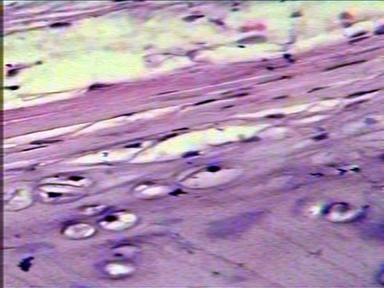

Laminario virtual IV. Tejidos cartilaginoso y óseo (5/20)

Cartílago hialino